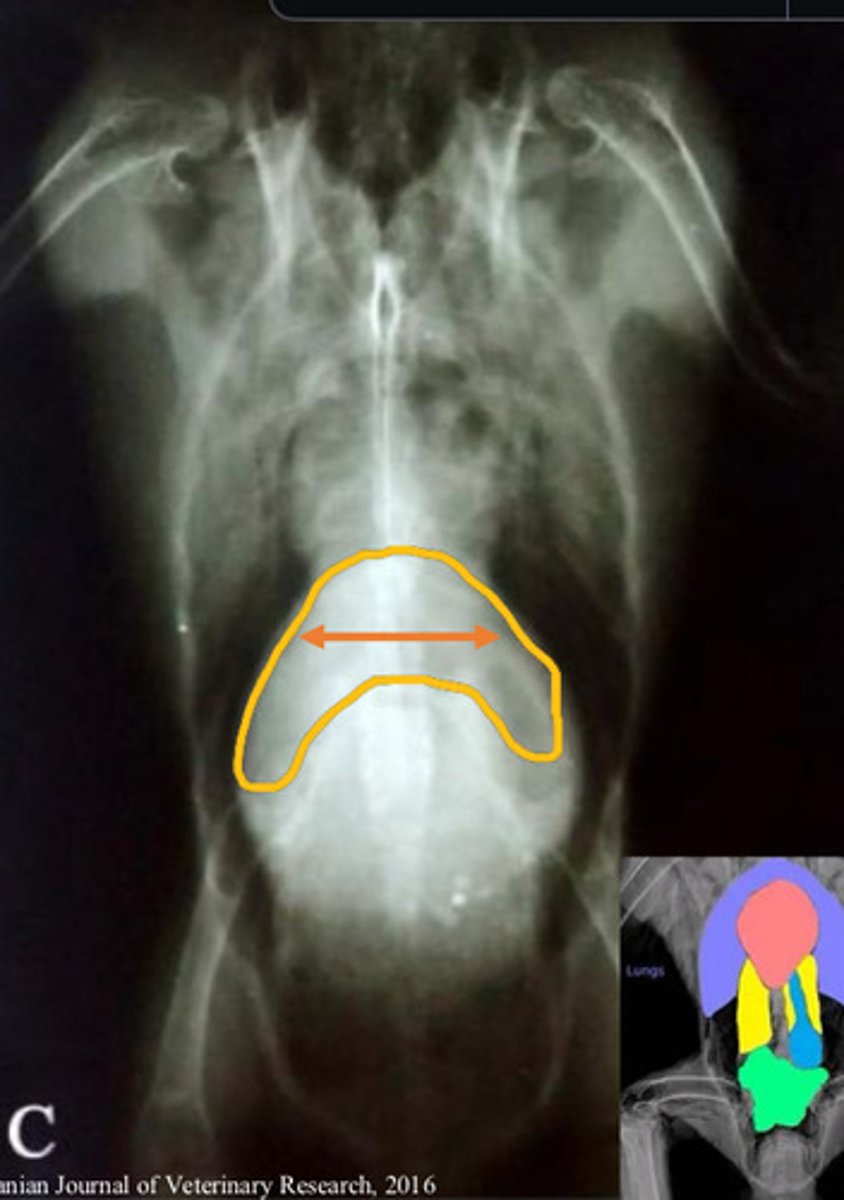

Paresis/paralysis/coelomic distention because femoral/obturator/sciatic nerves get compressed as they pass through the kidneys

Rads, histopath post morteum*

None (radiation?)

What species is commonly diagnosed with renal carcinoma?

What are the clinical signs, and why are these presented?

Dx?

Tx?